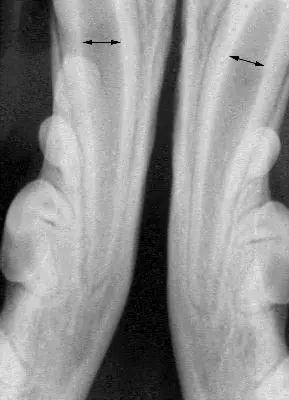

To maintain function, the best option for the initial treatment in this patient was determined to be crown reduction and vital pulp therapy (aka-“pulp cap”), which was performed. Figure one is a radiograph prior to the initial treatment, showing the wide root canal spaces that were present in the patient at that time (arrows). One reason vital pulp therapy was chosen for this patient is that, properly performed, the tooth remains vital, allowing the immature tooth to continue to mature and strengthen through the continued deposition of secondary (physiologic) dentin. Figure two is a post-op-radiograph showing the three layers of the restoration (MTA, glass ionomer and composite). Periodic follow-up radiographs on this patient had shown the lower canine teeth to be vital with continued maturation.

Figure one, showing the wide root canals present in young patients.